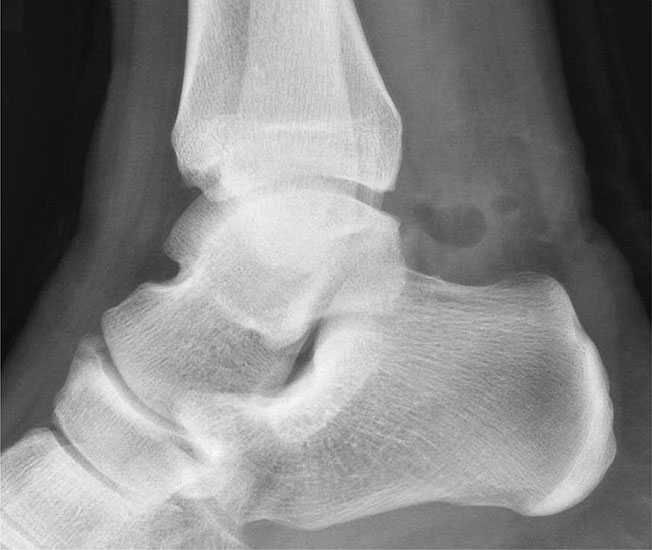

Reseziertes Os trigonum sowie prä- und postoperatives seitliches Röntgenbild nach arthroskopischer Entfernung eines Os trigonum.

Knochenresektat sowie präoperatives CT (Sagittal- und Transversalebene) und intraoperative Bildwandlerkontrolle im seitlichen Strahlengang nach arthroskopischer Entfernung multipler Ossikel am dorsalen OSG/USG.

Große osteophytäre Anbauten, welche die FHL-Sehne vollständig ummauern, sind ebenfalls sehr gut in der beschriebenen Technik adressierbar. Präoperatives CT und intraoperative Bildwandlerkontrolle im seitlichen Strahlengang (linke Seite).

• Bei Resektion von Osteophyten oder Entfernung eines Os trigonum postoperative seitliche Röntgenkontrolle des OSG.